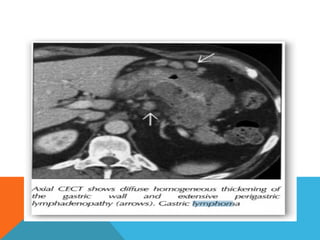

Computed tomography

Typically gastric lymphomas demonstrate marked

thickening of the stomach wall (2-4cm) with extensive

lateral extension of the tumour (i.e. along the wall of

the stomach) representing submucosal spread.

Computed tomography Typically gastriclymphomas demonstrate marked thickening of the stomach wall (2-4cm) with extensive lateral extension of the tumour (i.e. along the wall of the stomach) representing submucosal spread.

 Submucosal spreadmay  Encompasses the majority of the stomach giving a linitis plastica appearance.  Can extend across the pylorus into the duodenum and superiorly into the oesophagus.  uncommon for lymphoma to result in gastric outlet obstruction